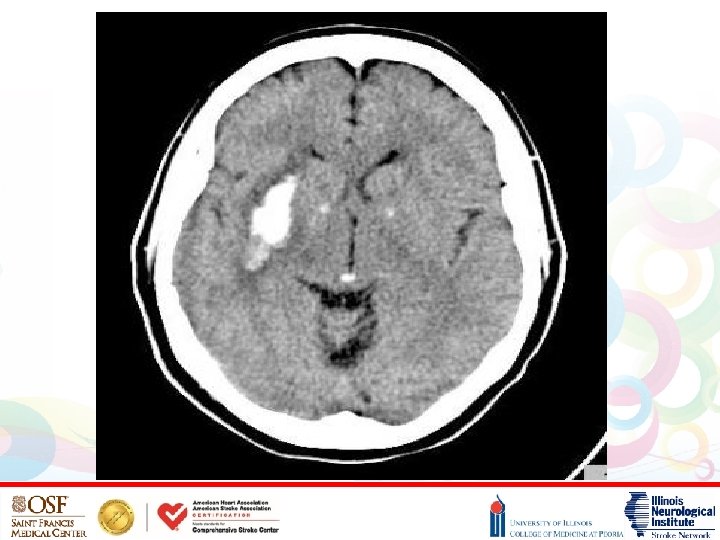

HYPERTENSIVE INTRACEREBRAL HEMORRHAGE • HTN is also the most common cause of intracerebral hemorrhages • Patho-physiologically, long-standing poorly controlled HTN leads to formation of microaneurysms of perforating arteries (Charcot-Bouchard aneurysms) • These small penetrating arteries can leak or rupture leading to hemorrhagic strokes • The most common locations for hypertensive hemorrhages include the basal ganglia (particularly the putamen), thalamus, pons, and cerebellum (Di. Muzio, Radiopedia, 2017)